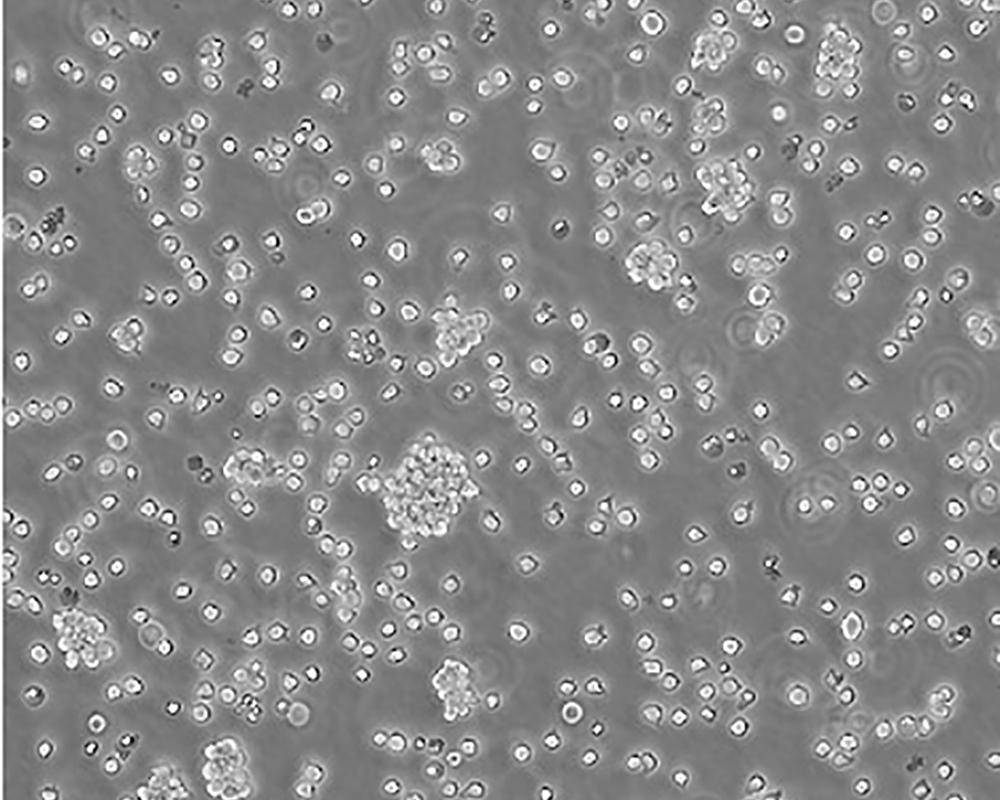

Jurkat, Clone E6-1 [Jurkat E6-1]

人T淋巴細(xì)胞白血病細(xì)胞

急性T淋巴細(xì)胞白血病;男性

Homo sapiens, human

生長特性

suspension

lymphoblast

該細(xì)胞是Jurkat-FHCRC細(xì)胞株(Jurkat細(xì)胞株的衍生)的一個克隆。Jurkat細(xì)胞株來源于一個14歲男孩的外周血。經(jīng)佛波酯和外源凝集素或抗T3單克隆抗體誘導(dǎo)后可產(chǎn)生大量IL-2(IL-2的產(chǎn)生需兩種類型的誘導(dǎo)劑);表達T細(xì)胞受體、CD3